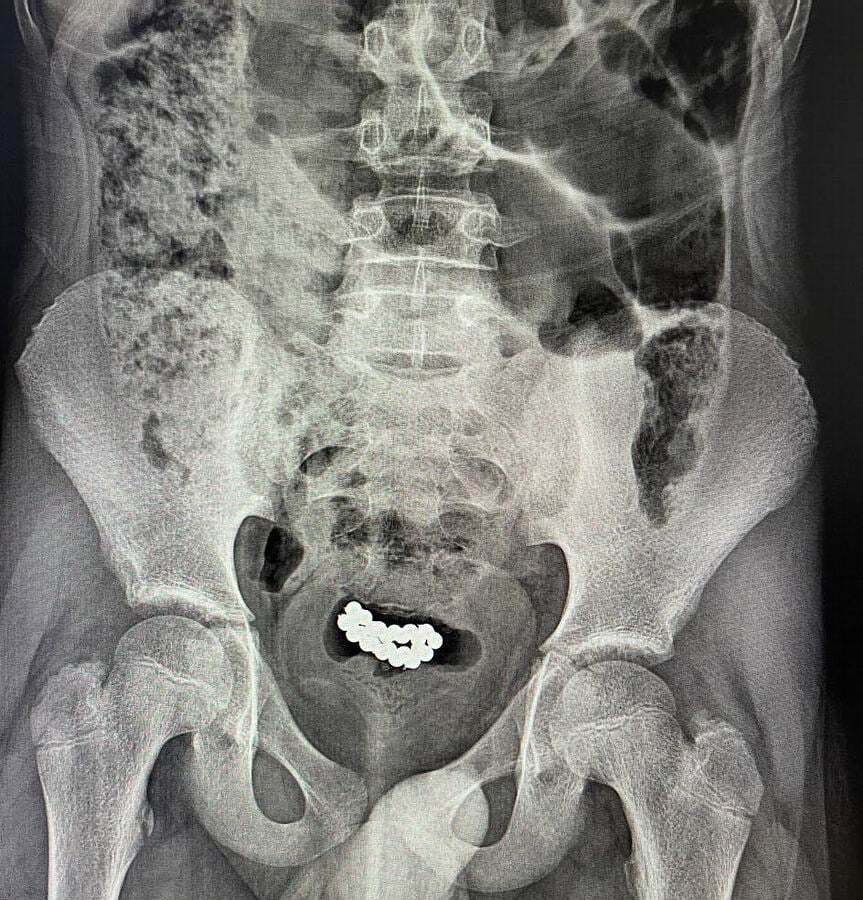

Йдеться про підлітків 10-15 років. Як розповіли в медичному закладі, 62 та 24 магнітні кульки було вилучено з сечових міхурів хлопців.

"В обох випадках було виконано цистотомію мінілапаротомним доступом із подальшим вилученням 62 та 24 магнітних кульок", – ідеться у повідомленні. В установі додали, що пацієнтів виписали з лікарні у задовільному стані, післяопераційний період у них пройшов без ускладнень.